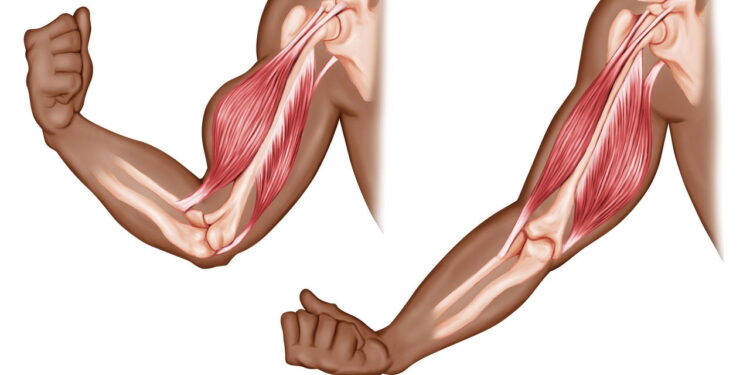

- Flexão de braço com elevação de pés: A flexão tradicional pode ser potencializada ao elevar os pés em uma cadeira ou banco. Essa variação aumenta a dificuldade e ativa de forma mais intensa o peitoral, ombros e tríceps.

- Remada unilateral com galão de água: Para trabalhar as costas e os bíceps, o galão de água funciona como um halter improvisado. Basta apoiar um joelho em uma superfície estável e puxar o galão em direção ao corpo, alternando os lados.